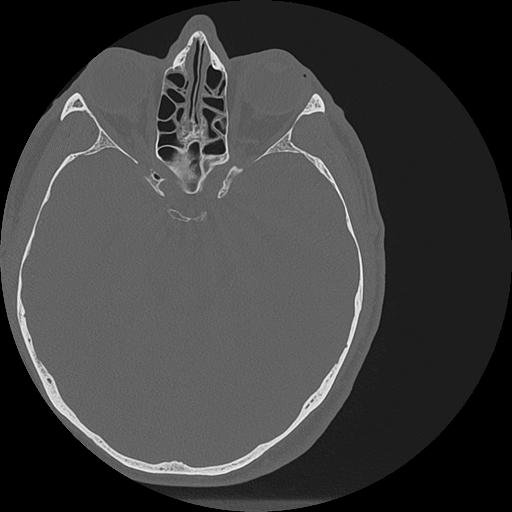

7 HUESO,,Vol,0.5,HUESO,,